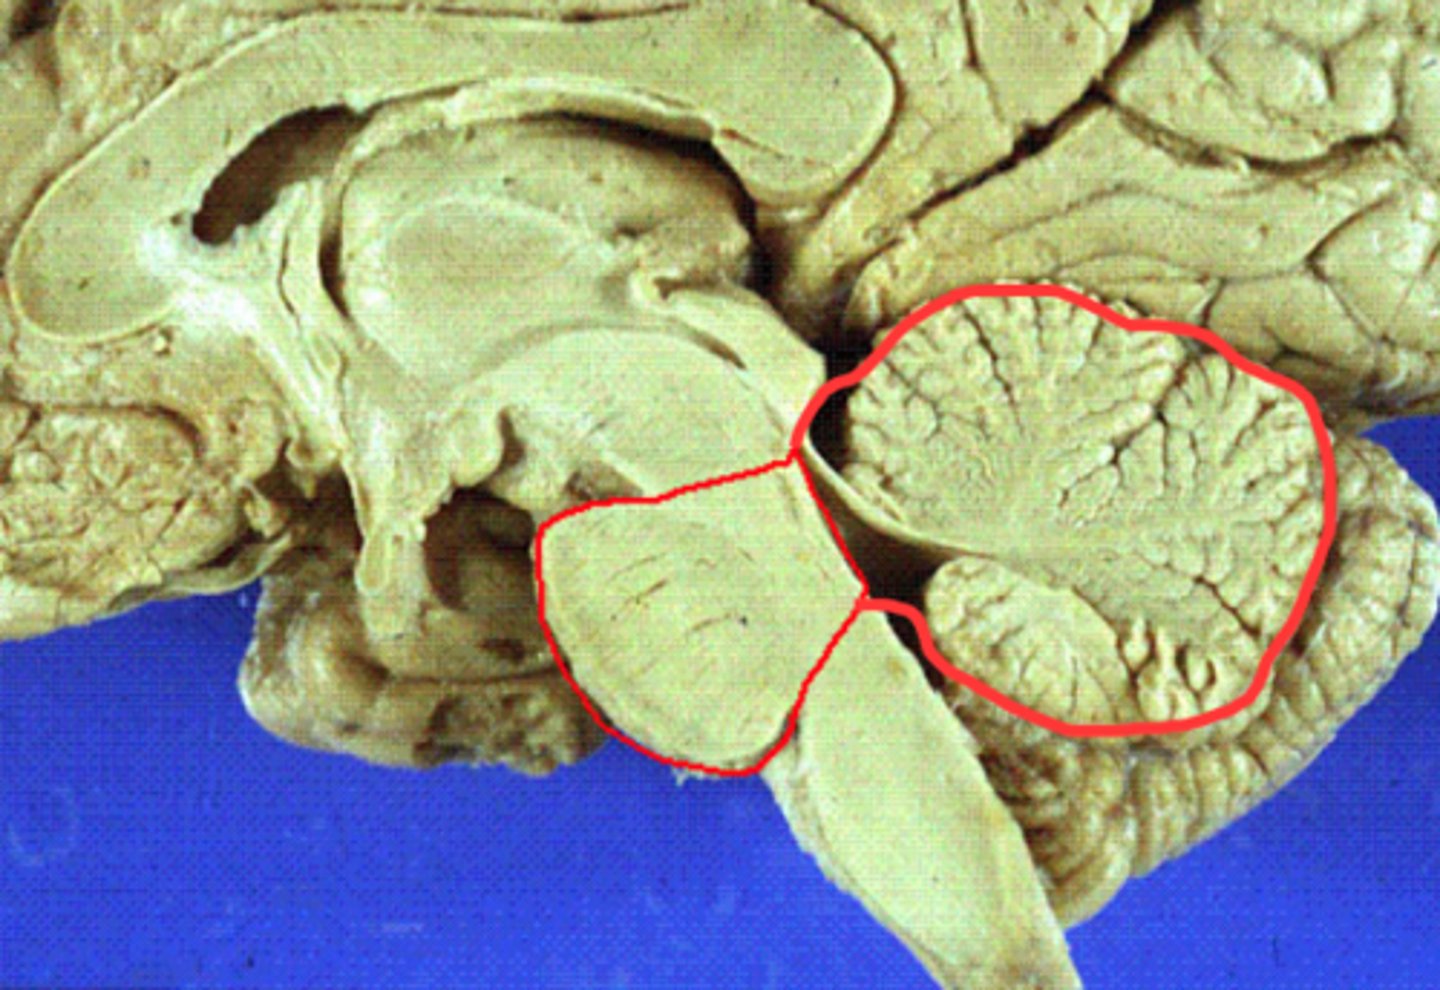

tentorium cerebelli

2nd largest, crescent-shaped, separates cerebrum (occipital lobes) from cerebellum (arrow #5)

falx cerebelli

seperates the two hemispheres of the cerebellum. it lies inferior to the tentorium cerebelli, separating cerebellar hemispheres (arrow #7)